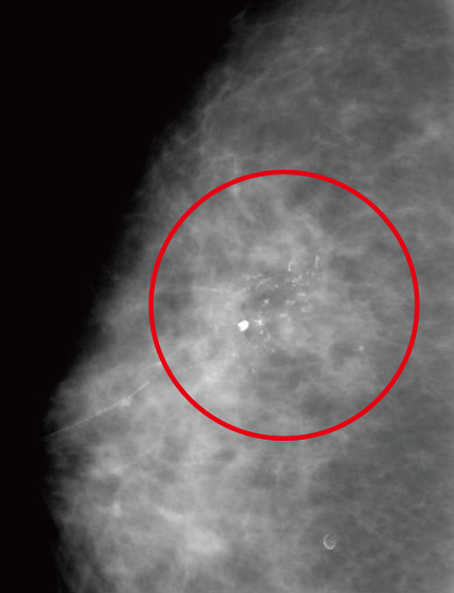

• 可藉由乳房篩檢攝影發現微小鈣化點等乳癌初期徵狀。

篩檢性乳房攝影(Screening mammography)

左右兩側乳房各要照兩張X光片,分別為頭腳向(由上往下照)及斜位向(由側邊照)